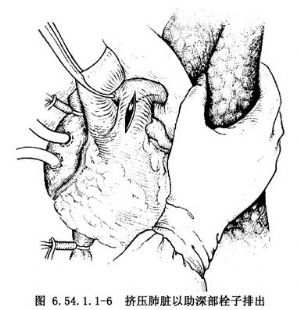

4.切开双侧胸膜腔,以手挤压肺脏以助深部栓子的排出(图6.54.1.1-6),也可用Fogarty气囊导管伸入双侧肺动脉牵拉出残存的栓子(图6.54.1.1-7)。切开右心房、右心室,检查有无存留在心腔内的栓子或附壁血栓、血块,予以取出,冲洗心腔。